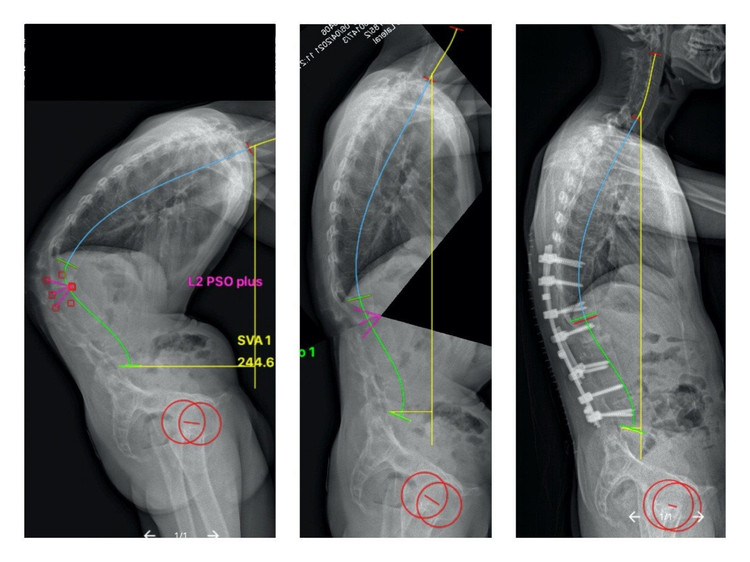

Hình ảnh bệnh nhân trước mổ (hình bên trái) với cột sống còng gần 90 độ và sau mổ (hình bên phải) với cột sống đã được chỉnh thẳng

Kết quả chụp cắt lớp và cộng hưởng từ cho thấy, bệnh nhân bị gãy trật đốt sống L1/2 trên nền viêm dính cột sống và góc còng của bệnh nhân là gần 90 độ.

Ngay sau phẫu thuật, bệnh nhân đã có thể nằm ngửa do cột sống đã được chỉnh thẳng, bắt đầu ngồi dậy từ ngày thứ ba và đi đứng từ ngày thứ năm. Hình ảnh X-quang sau phẫu thuật cho thấy phẫu thuật viên đã chỉnh được hơn 60o của góc còng ban đầu và giúp phục hồi lại dáng đứng thẳng.